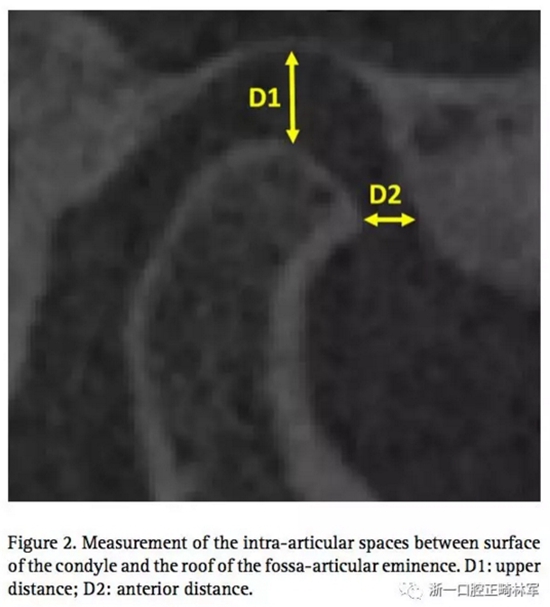

通過這個正常TMJ關節(jié),設計其他三個模型,包括有無??墊的,有無關節(jié)盤前移位的。因此,志愿者需要佩戴??墊進行CT掃描,去分析上頜距離D1和關節(jié)間隙(關節(jié)面和關節(jié)窩之間)上部分距離D1和前部分距離D2。(圖2)可以發(fā)現(xiàn),因為磨牙間2mm的??墊,前關節(jié)腔有少量的增長,還有髁突輕微的旋轉(zhuǎn)。